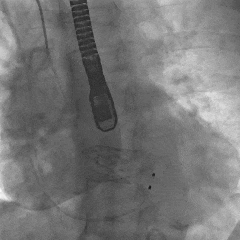

最终瓣膜位置稳定

TEE长轴:瓣膜深度可

TEE短轴:瓣膜展开良好,仅少量瓣周漏

-

主瓣峰值流速由术前4.2m/s降至术后1.69m/s

主瓣峰值压差由术前70mmHg降至术后11mmHg